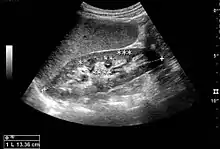

- Figure 5. Simple renal cyst with posterior enhancement in an adult kidney. Measurement of kidney length on the US image is illustrated by '+' and a dashed line.[1]

- Figure 6. Complex cyst with thickened walls and membranes in the lower pole of an adult kidney. Measurements of kidney length and the complex cyst on the US image are illustrated by '+' and dashed lines.[1]

- Figure 7. Advanced polycystic kidney disease with multiple cysts.[1]